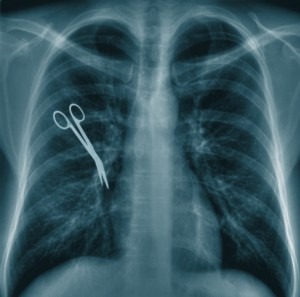

The consequences of having an object left behind are extremely serious. A sharp object, such as a clamp, a pair or scissors, or a scalpel, can cut into internal flesh and even puncture organs and cause serious internal bleeding. Other objects, such as gauze or sponges, can very quickly lead to deadly infection, years of pain, and other life-threatening complications. Sadly, many patients deal with these post-operative complications thinking that they are normal – and never guessing that they could be carrying a souvenir from their hospital visit.